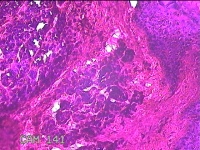

右侧头皮结节

性别

男

年龄

28岁

临床诊断

皮肤良性肿瘤

一般病史

发现右侧头皮结节3个月余,无明显疼痛及不适。

标本名称

大体所见

灰白暗红色组织1.5x1.2x0.8cm一块,表面带梭形皮肤1.5x1cm,皮下见结节1.5x1x0.3cm一个,结节表面有少许毛发,切开结节呈实性,切面灰白粉红色,质软。